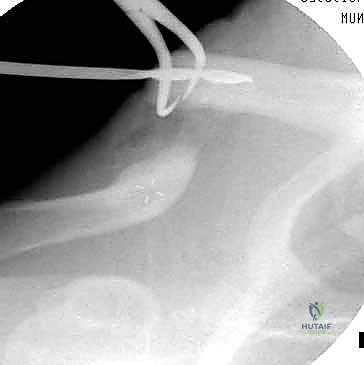

الخلاصة الطبية السريعة: تثبيت كسور الترقوة داخل النخاع (Intramedullary Fixation) هو إجراء جراحي حديث ومتطور، يستخدم مسمارًا أو قضيبًا مرنًا من التيتانيوم لتثبيت عظم الترقوة من الداخل (داخل القناة النخاعية للعظم)، مما يوفر استقرارًا ميكانيكيًا فعالًا وتعافيًا أسرع بكثير من الطرق التقليدية. يتميز هذا العلاج بكونه أقل بضعاً (Minimally Invasive)، حيث يتطلب شقوقًا جراحية صغيرة جدًا، مما يضمن نتائج تجميلية أفضل ويقلل من خطر تلف الأنسجة المحيطة. ويعد هذا الإجراء خيارًا ممتازًا ومثاليًا لحالات مختارة من كسور منتصف الترقوة المنزاحة.

هذه هي التقنية المتقدمة التي يتميز بها البروفيسور محمد هطيف. بدلاً من وضع شريحة خارجية، يتم إدخال مسمار أو قضيب مرن (مثل مسمار التيتانيوم المرن TEN أو مسامير مصممة خصيصًا للترقوة) داخل تجويف العظم (القناة النخاعية).